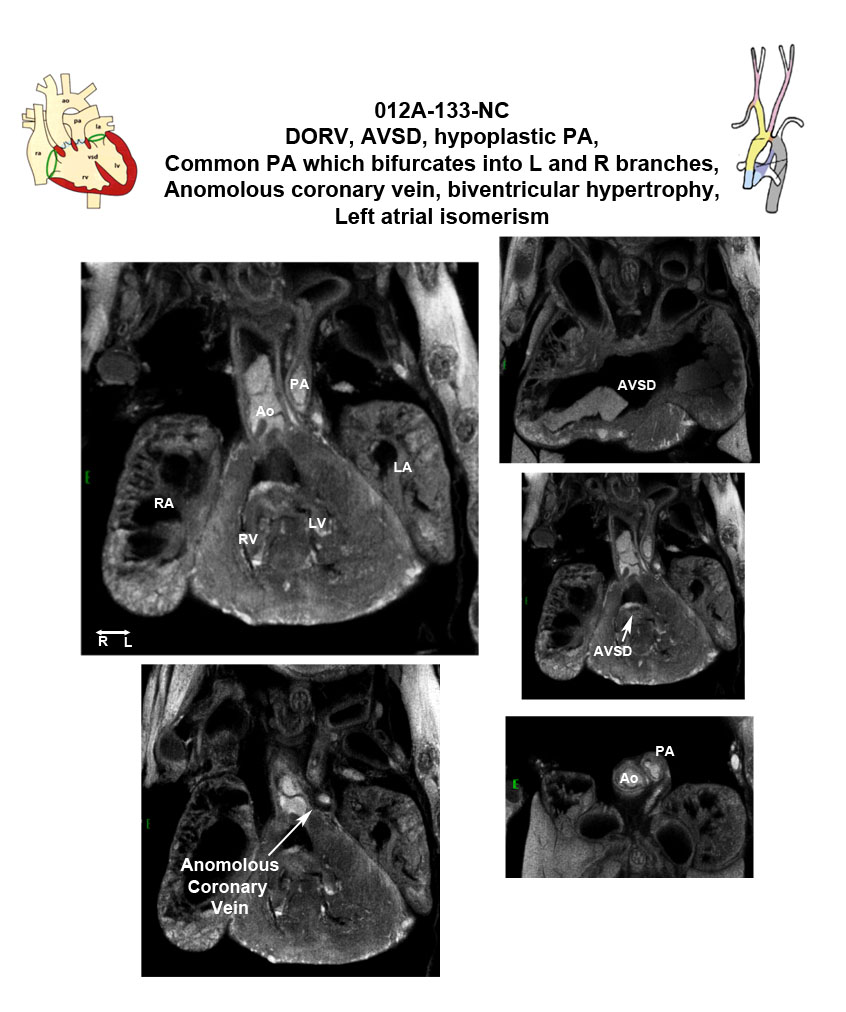

Cplane1b2b012Clo ciliogenesis and planar polarity effector 1; Bench to Bassinet Program (B2B/CVDC), mutation 012 Cecilia Lo

Cplane1b2b012Clo/Cplane1b2b012Clo C57BL/6J-Cplane1b2b012Clo